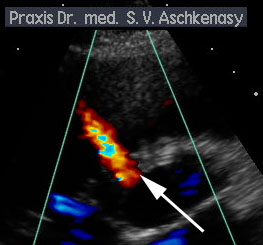

Das oben gezeigte Bild zeigt einen sogenannt 'perimembranösen VSD', der Ventrikel Septum Defekt steckt im membranösen Septum direkt unterhalb der Aortenklappe. In diesem Bereich hat das membranöse Septum auch ein Aneurysma (eine Ausweitung) (s. Pfeil).

Klicken Sie auf den Clip um den Blutfluss über den VSD zu sehen.